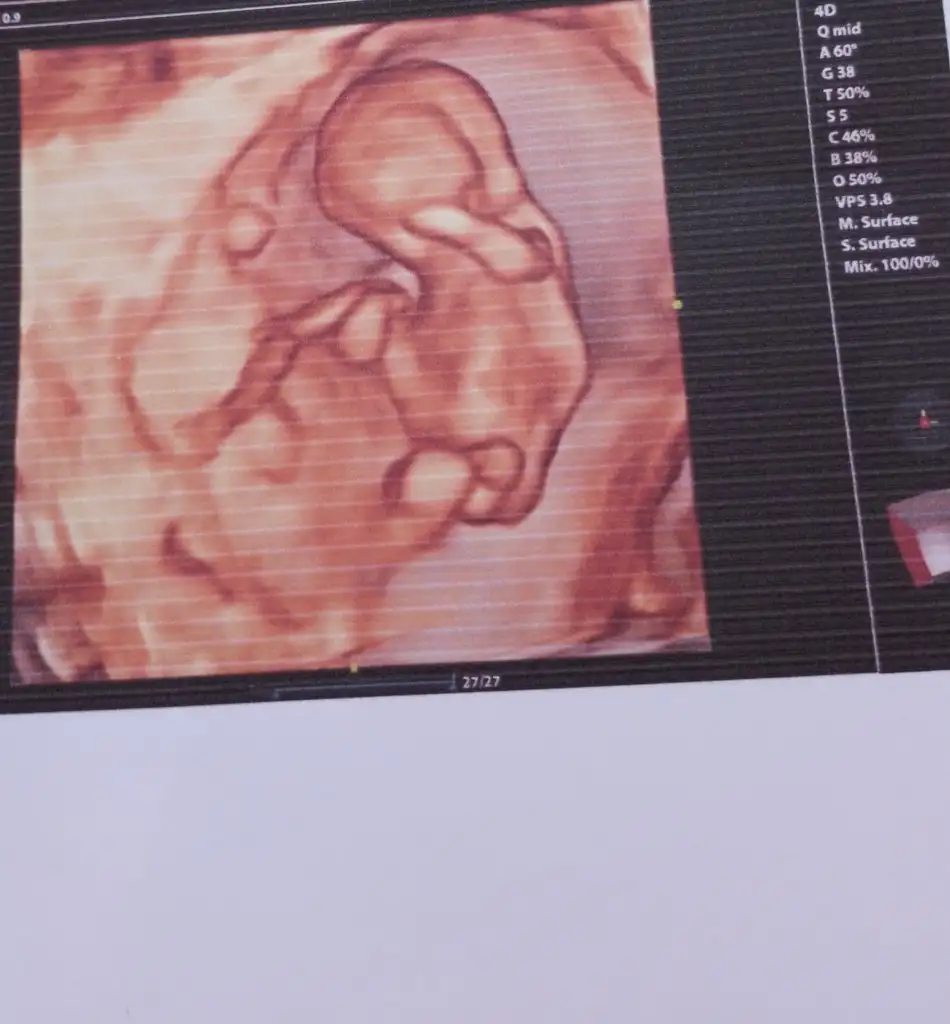

Kizlar tahmin istiyorum sence ne geliyor

Eklentiler

• IMG_20230921_125350.webp

IMG_20230921_125350.webp

9,5 KB · Görüntüleme: 97